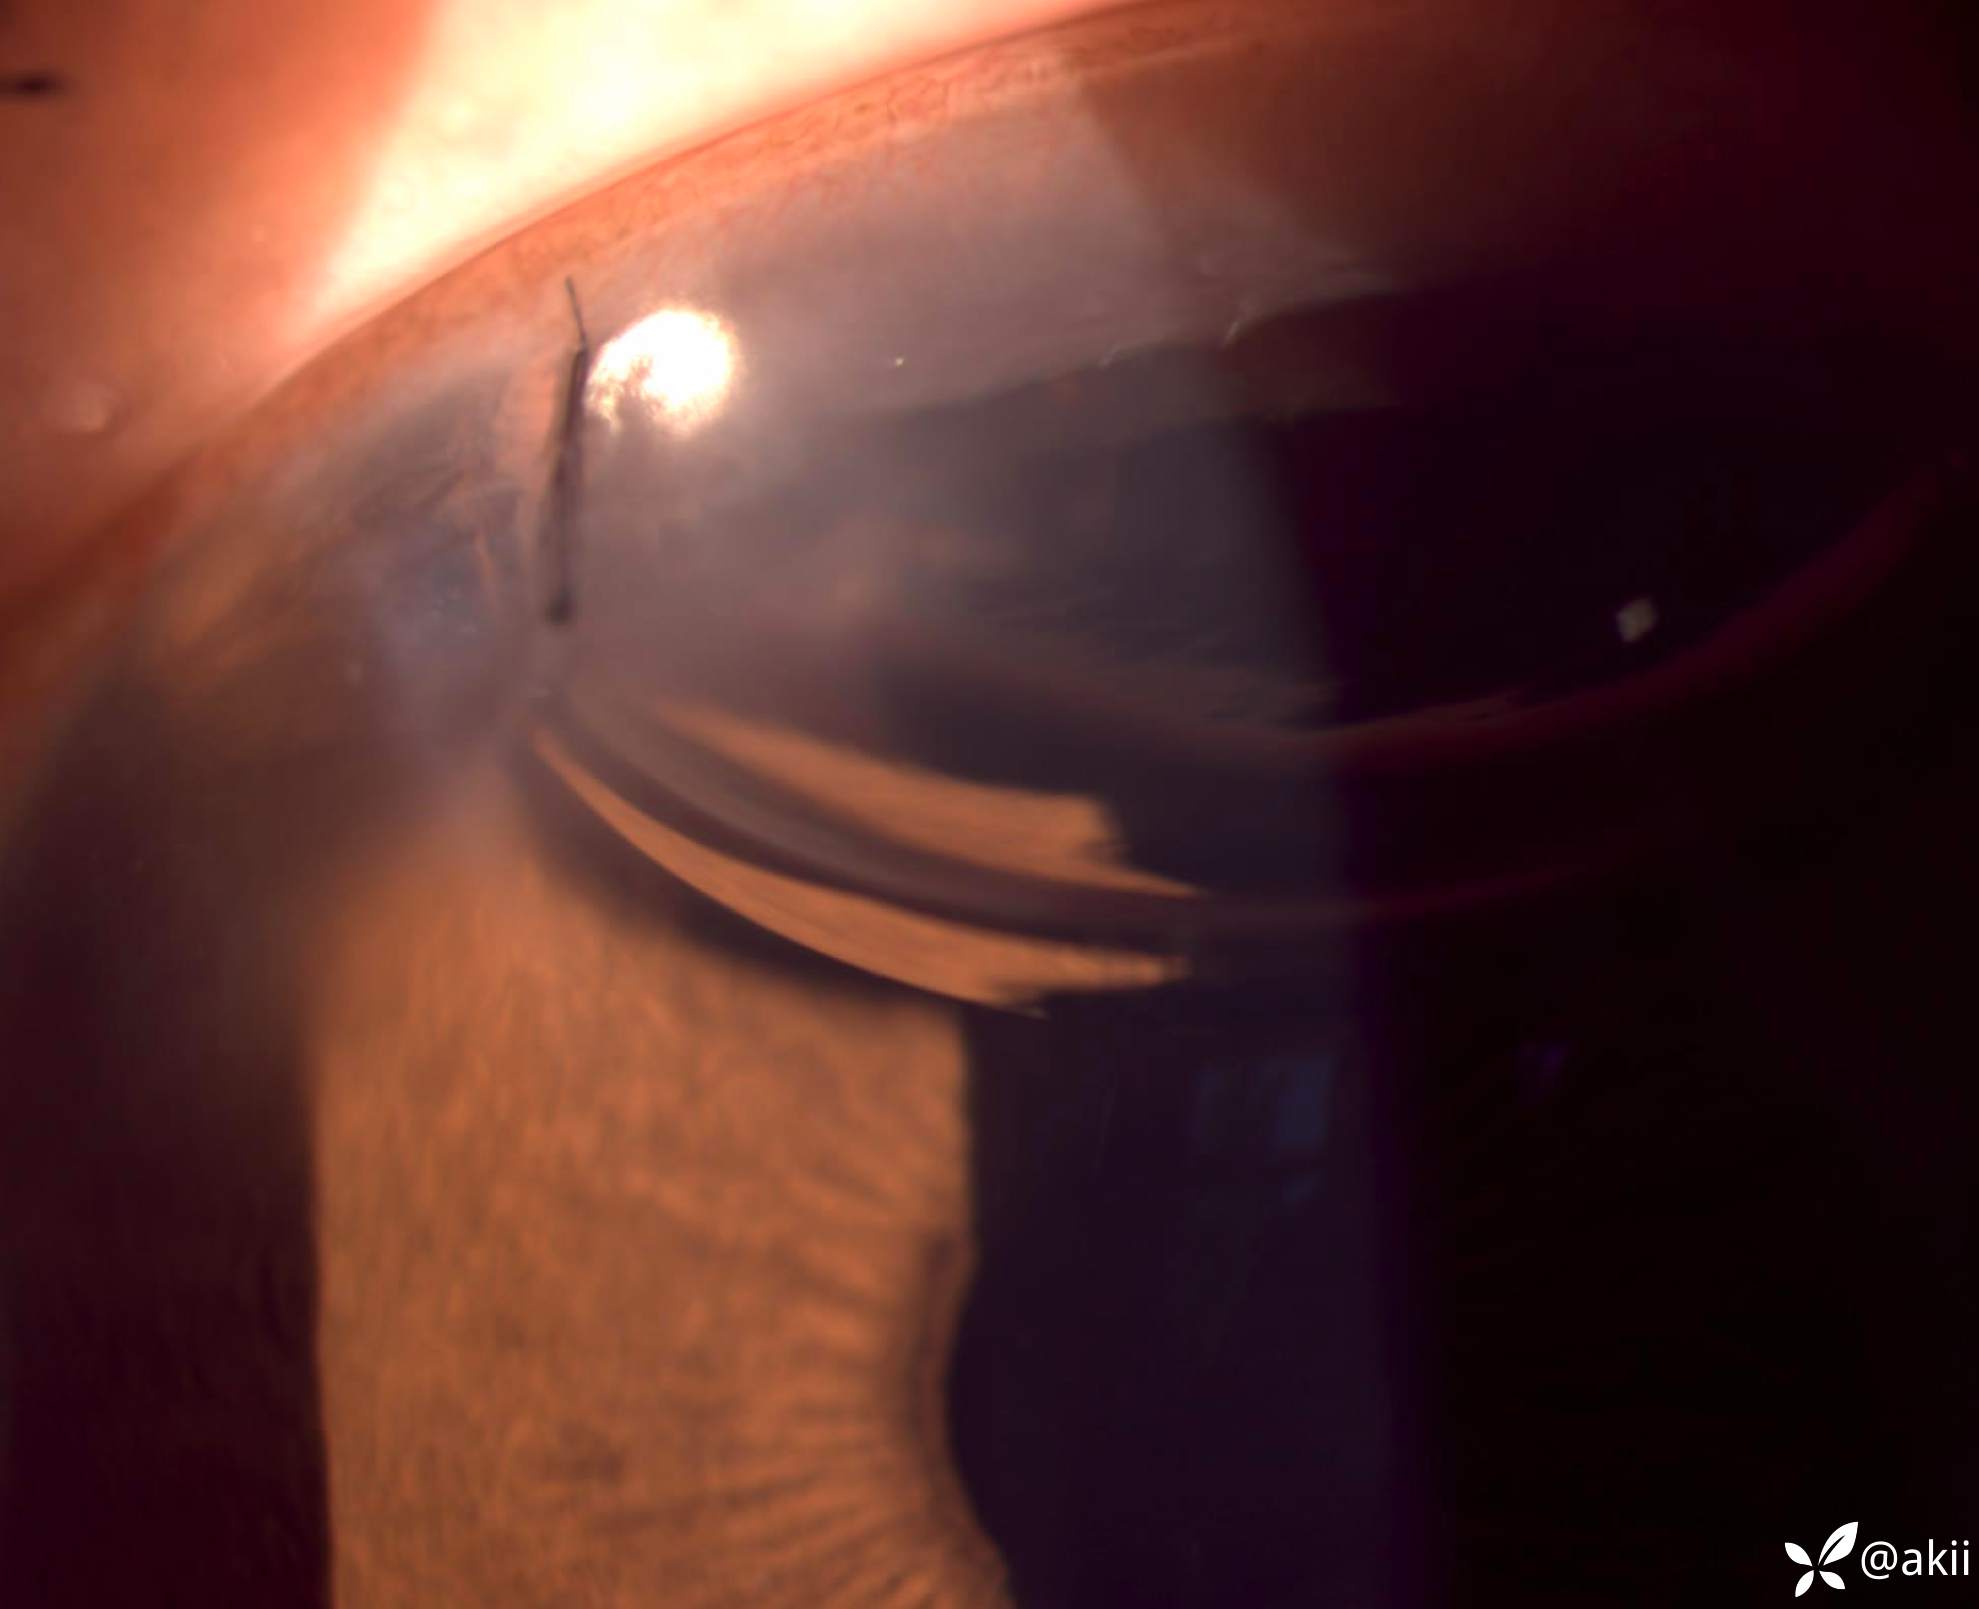

拆线前4.5D角膜散光,矫正视力0.4

病人术后1天,诉os重影,视力不满意,裸眼远/中/近视力分别是 0.4/0.25/0.4,矫正视力-0.25/-3.00*60→0.4,矫正视力不提高

遂行切口缝线拆除,拆除后即刻视力满意。裸眼远/中/近视力分别是 0.8/0.8/1.0,矫正视力-1.25/-0.75*85→0.8+,矫正视力不提高